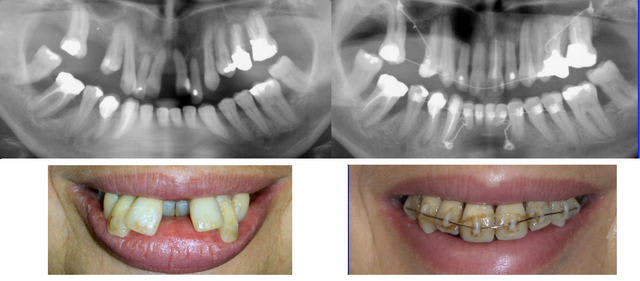

Cette gentille dame est donc venue hier après-midi comme je le lui avais demandé m’apporter les rétroalvéolaires (en argentique) qui venaient d’être réalisée par le confrère parodontiste. J’en ai profité pour lui faire avec un mois d’avance sur la date prévue une radio panoramique numérique. Comme je n’ai vraiment pas le temps de les numériser maintenant, j’ai téléphoné au parodontiste pour lui demander ce qu’il en pensait. Sa réponse m’a réjouit.

Il est très satisfait de l’état actuel, tout est stabilisé, sous contrôle, la mobilité des dents s’est considérablement réduite. Il y a de l’os. Il n’y a pas de signe prévisible de dégradation de la situation dans les prochains temps et une attelle linguale étendue de contention pourra durer relativement longtemps.

La patiente a rejeté l’option chirurgicale, nous allons donc nous en tenir là pour les déplacements dentaires et tout déposer en début d’année prochaine. Le traitement orthodontique aura duré un an. Comme d’habitude, mon confrère supprimera la mécanique lui-même le jour où il aura collé les attelles étendue en palatin. Je déposerai ensuite moi-même les ancrages osseux que j’ai mis en place.

Photos jointes, le cas actuellement et la panoramique prise hier soir. Dans quelques temps, lorsque tout sera déposé, je montrerai les photos finales.